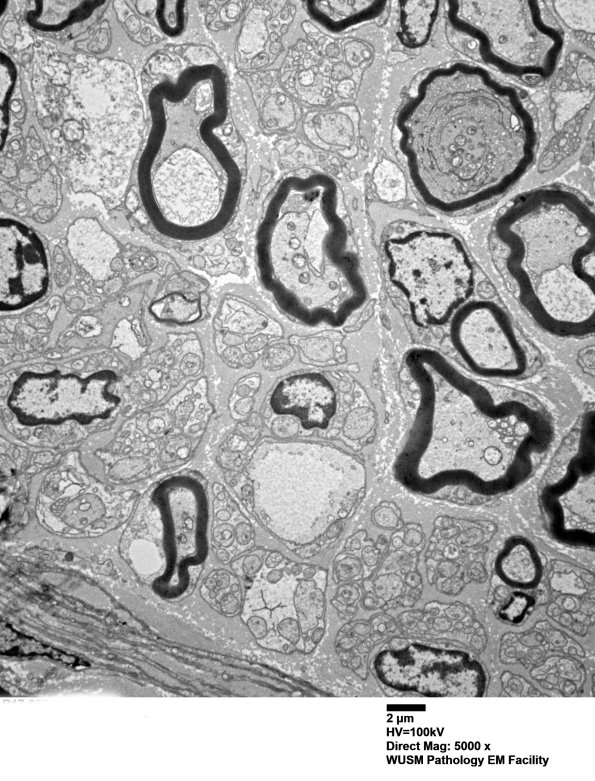

In this individual there are significant populations of both large and small myelinated axons as well as pale pre-myelinated axons. (electron micrograph)